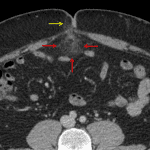

- Fat stranding in the greater omentum immediately subjacent to a small fat-containing right periumbilical hernia

- Omental infarct

Findings suggestive of omental infarct. The proximity to a small fat-containing right periumbilical hernia raises the possibility of vascular compromise related to the hernia.